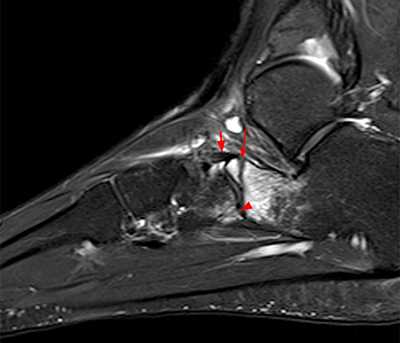

Рентгенологическое исследование

Для диагностики повреждения сустава Шопара делают рентген, КТ и МРТ. На передне-задней рентгенограмме определяют величину пяточно-кубовидного угла. Проводят одну касательную к наружному краю кубовидной кости и вторую касательную к наружному краю пяточной кости. В норме угол между касательными колеблется в пределах от 0 до 5°. Увеличение угла свидетельствует о нарушении стабильности пяточно-кубовидного сочленения. КТ во фронтальной и сагиттальной плоскостях позволяет выявить дефект суставных фасеток, смещение костей при вывихе и фрагментацию костей при переломе. КТ, по сравнению с рентгенографией, является более информативным методом диагностики. МРТ позволяет выявить дефекты отдельных связок.

Рис. 6. Отрывной перелом по тылу таранной кости на границе с суставом Шопара